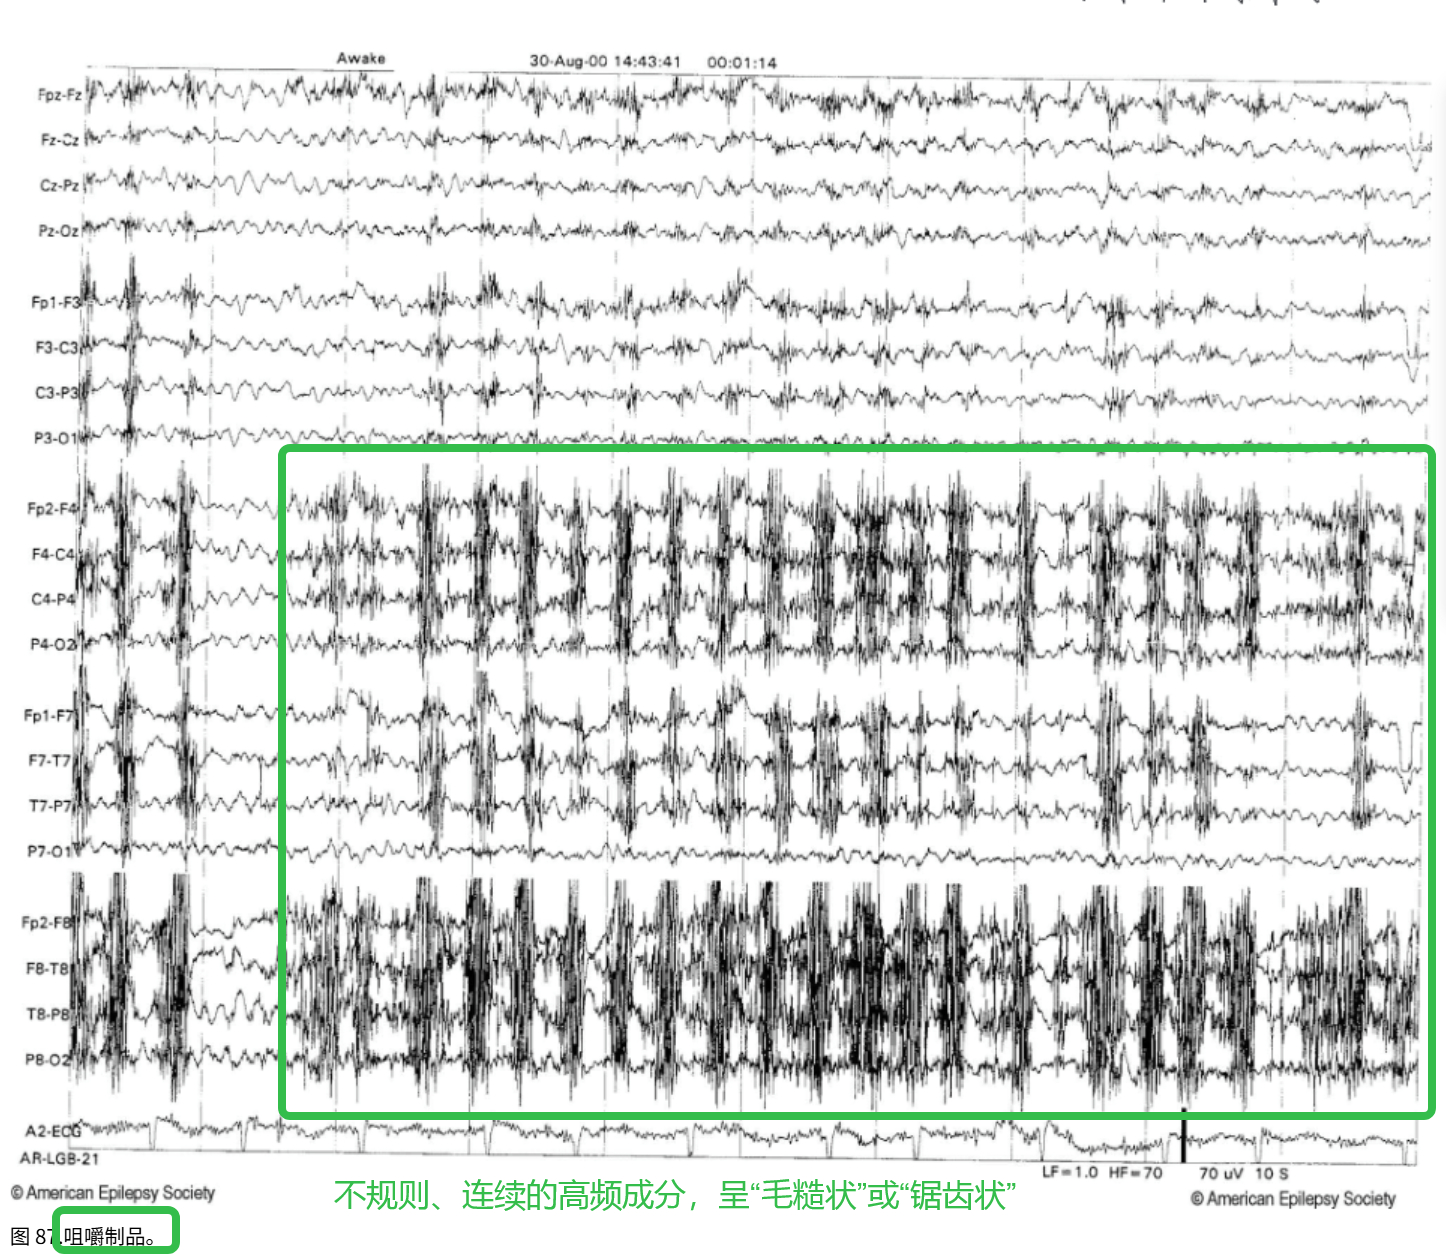

肌电伪迹是由头面部或颈部肌肉活动(如额肌、颞肌、颈肌等)产生的电信号,混入脑电图中形成干扰。

- 与眼电伪迹不同,肌电伪迹通常 频率高、波幅不规则 。

- 常出现在 EEG 采集过程中受试者紧张、皱眉、咀嚼、说话或头部移动时。

来源:额肌活动(皱眉、抬眉)、颞肌或颈肌(咀嚼、说话、吞咽、颈部张力)、头部动作(抖动、翻身)……

频率:高频,一般 20–100 Hz

振幅:中等到高,一般 20–200 μV,但不规则